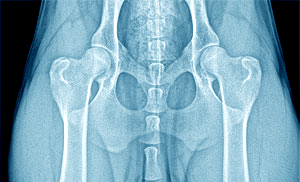

Dysplázia bedrového kĺbu - DBK

w hips excellentDysplázia bedrového kĺbu (DBK) je degeneratívne ochorenie bedrového kĺbu charakterizované nezvratnými zmenami kĺbovej jamky a hlavice stehennej kosti. Ide o vývojové ochorenie.

Choroba je spôsobená nedostatočným vývinom kĺbovej jamky a bedrového kĺbu. Nerovnomerný rast kostí spôsobí poškodenie chrupavkovitých častí. Zmeny na bedrových kĺboch je možno dobre pozorovať na RTG snímkach. DBK postihuje najčastejšie veľké a obrie plemená, môže sa však vyskytovať u ktoréhokoľvek plemena.

Diagnostikuje sa pomocou RTG snímku. Zoznam certifikovaných posudzovateľov DBK, DLK, pre vyhotovenie kvalitných snímkov. Snímok musí byť kvalitný a označený tak, aby nemohol byť zamenený. Snímok sa zasiela klubom určenému veterinárnemu lekárovi, ktorý vyhodnocuje snímky v rámci SR.

RTG snímok DBK

Pes leží na chrbte s natiahnutými panvovými a hrudníkovými končatinami tak, aby telo psa tvorilo os. Panvové končatiny sa ťahajú rovnobežne smerom dozadu. Pri RTG DBK je pes v narkóze, aby bolo zabezpečené dostatočné uvoľnenie svalov na končatinách. Na snímke musí byť dobre viditeľná celá panva, krížová kosť, stehnové kosti spolu s kolennými kĺbmi.